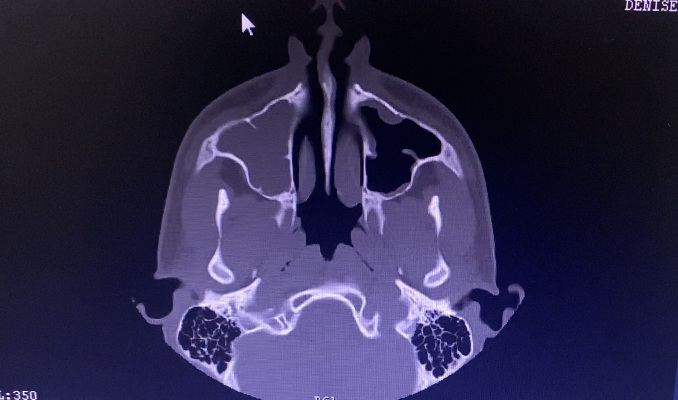

Пациенту, с согласия мамы, было произведено КТ ППН, по результатам которого был поставлен диагноз: «Острый полисинусит. Искривление перегородки носа. Вазомоторный ринит».

Снимки до начала лечения